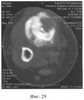

Аппарат внешней фиксации с левой голени демонтирован через 3 месяца после операции при клинико-рентгенологической картине сращения перелома. Аппарат внешней фиксации с правой голени демонтирован через 7 месяцев после операции при клинико-рентгенологической картине сращения перелома (фиг.20-25 – результат лечения). При рентгенологическом и томографическом контроле в трансплантатах отмечалось постепенное нарастание плотности костной ткани с формированием костной мозоли на всем протяжении между трансплантатом и костными фрагментами (фиг.26-29 – динамика данных компьютерной томографии правой голени: отмечается нарастание плотности костной ткани в области трансплантатов и формирование регенерата между смещенным трансплантатом и костными фрагментами; фиг.30-33 – динамика данных компьютерной томографии левой голени: отмечается нарастание плотности костной ткани в области трансплантатов и формирование регенерата между трансплантатом и костными фрагментами).

При оценке результатов томографического исследования в динамике отмечено быстрое нарастание плотности костной мозоли между дистальным и проксимальным фрагментами (фиг.56 – динамика томографической картины на уровне контакта костных фрагментов), что позволяет говорить об остеоиндуктивном воздействии предложенного биотрансплантата. В то же время в области трансплантата также отмечены очаги остеогенеза с нарастанием их плотности в динамике и включением в костную мозоль (фиг.57 – динамика томографической картины на уровне трансплантата).